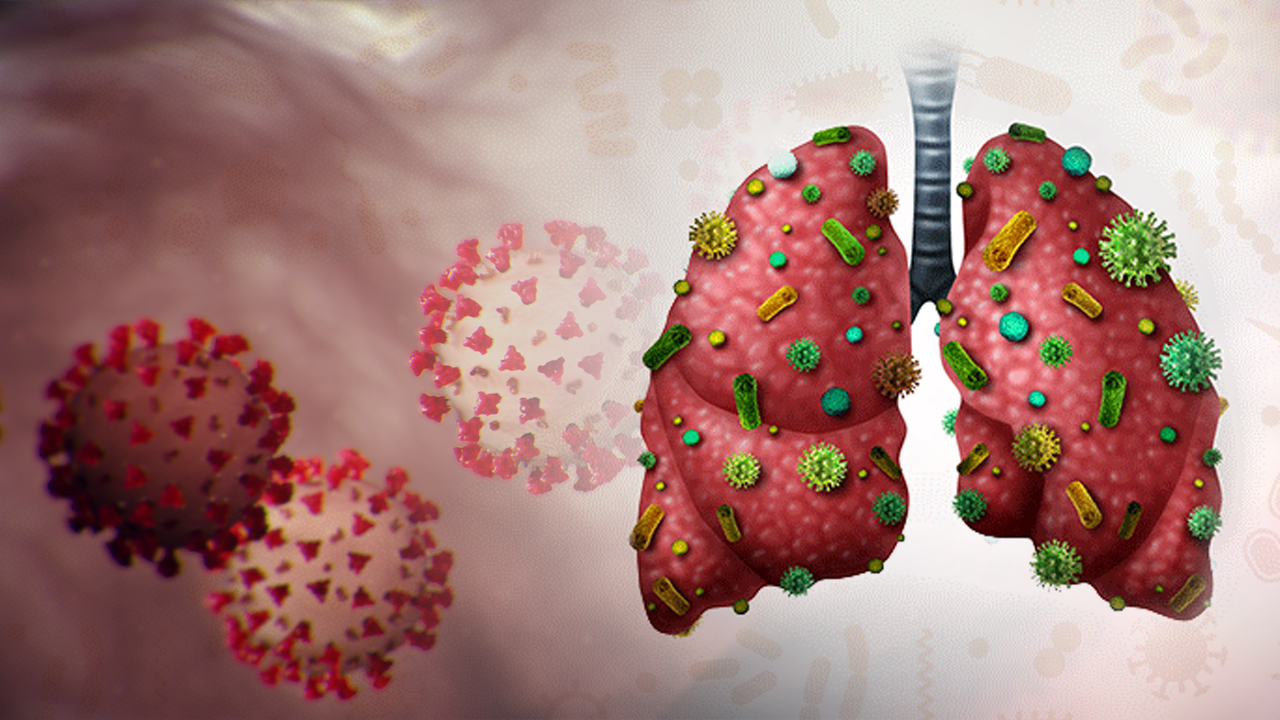

করোনার কামড়ে শক্ত হয়েছে ফুসফুস

কোভিড-১৯ আক্রান্তদের ফুসফুস ক্ষতিগ্রস্ত হতে পারে

করোনাভাইরাস: হাসপাতাল থেকে ফেরার ৩ মাস পরেও ফুসফুসে থাকছে সংক্রমণের জের, বলছে গবেষণা